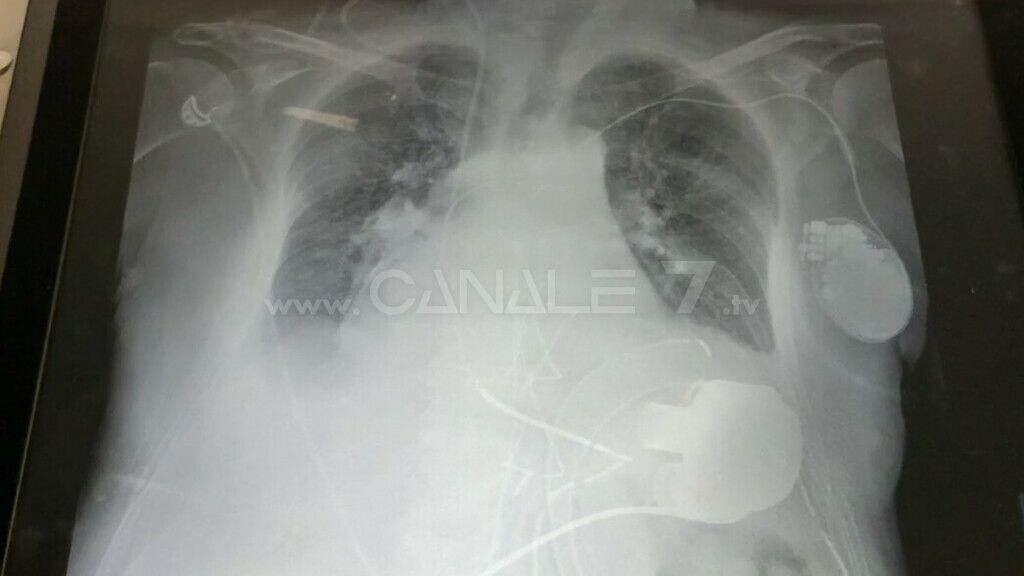

Un cuore artificiale, un sistema di assistenza ventricolare di ultimissima generazione, è stato impiantato con successo al Policlinico di Bari per salvare la vita a un paziente di 65 anni proveniente dalla Basilicata con scompenso cardiaco avanzato, refrattario alla terapia medica e con indicazione negativa per il trapianto di cuore. L’intervento è stato realizzato dall’equipe del prof. Aldo Milano, direttore dell’unità operativa di cardiochirugia dell’azienda ospedaliero universitaria barese.

Il dispositivo di assistenza ventricolare (LVAD) preleva il sangue dal ventricolo sinistro e lo pompa ossigenato nell’aorta, utilizzando il nuovo sistema a levitazione magnetica impiantato per la prima volta in Puglia.

La pompa del dispositivo di assistenza meccanica al circolo, infatti, viene impiantata all’interno del corpo mediante l’intervento cardiochirurgico, è alimentata da batterie collegate a un piccolo controller esterno attraverso un cavo che fuoriesce dall’addome del paziente.